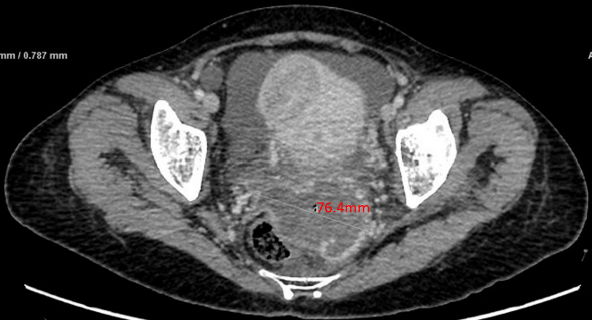

绒患者,张某,女,51岁。主诉:停经伴左中下腹痛4+月 现病史:患者既往月经规律,周期30天,LMP 2021年7月14日。停经后无恶心、呕吐等不适。G3P2A1,足月顺产两次,末次妊娠为7年前,行人工流产终止妊娠,此后以避孕套避孕。4月余前无明显诱因出现左中下腹隐痛,休息后可缓解,无进行性加重,无排便习惯改变等。2021年10月30日就诊于当地医院,彩超示:肝内多发高回声结节,血管瘤?其他不排。左侧腹腔内低回声包块,性质待定,腹腔少量积液。CT提示:左侧腹部占位性病变,考虑来源于腹腔,性质待查,纤维瘤?间质瘤?其他?转诊至当地上级医院,行电子直-结肠镜示:乙状结肠病变性质待查。CT示:1.左侧腹腔内肿块灶:间质瘤?炎性肌纤维母细胞瘤?2.肝内多发结节灶:转移瘤;3.子宫肌层内结节灶:子宫肌瘤?4.右侧附件区不规则肿块:粘液囊腺瘤可能性大;5.宫颈左后上方结节灶:转移瘤?6.盆腔少量积液;7.腹腔内多发小淋巴结。在超声引导下行左上腹腹腔肿块穿刺活检,穿刺组织3条,全部为凝固性坏死组织,倾向恶性肿瘤。2021年11月1日血清hCG 830 mIU/ml。2021年11月8日再次转诊至广州某医院,行肝部肿物穿刺,病理示:(肝肿物)结合免疫组化[β-HCG(+),GATA-3(+),p63(部分+)]考虑为绒毛膜上皮癌可能性大。2021年11月17日血清hCG >100万 mIU/ml。为进一步诊治,请我院进行院际会诊后,予以EP方案化疗1程后转入我科。 月经婚育史:12岁初潮,周期30天,经期5天,LMP 2021年7月14日,量中,无痛经。生育史同前。 个人史和家族史:无特殊。 体格检查:T 36.3℃,P 102次/分,R 20次/分,BP 120/80mmHg,身高156cm,体重50kg。左侧中下腹部触诊可及一约15cm×10cm边界不规则的质硬肿物,活动度差,轻压痛。 妇科检查:外阴未见异常;阴道通畅,各壁未见紫蓝色结节;宫颈正常大小,光滑,无接触性出血;宫体前位,大小基本正常,活动度差;双侧附件区未及异常肿物;三合诊:道格拉斯窝处可及一边界欠清肿物,触痛不明显,双侧宫旁无增厚,指套退出直肠无血染。 辅助检查: 全腹部CT平扫+增强+三维重建:腹腔大量积液,脂肪间隙模糊并多发渗出;肝内多发转移瘤并部分瘤内出血;左中腹肝胃间隙、脾胃间隙及子宫直肠间隙肿块,考虑转移瘤。 胸部CT:双肺散在实性结节,考虑转移瘤。 头颅MR平扫+增强:未见异常。